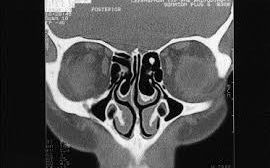

Currently, computed tomography (CT) is accepted as the gold standard in the radiological diagnosis of paranasal sinus pathologies.